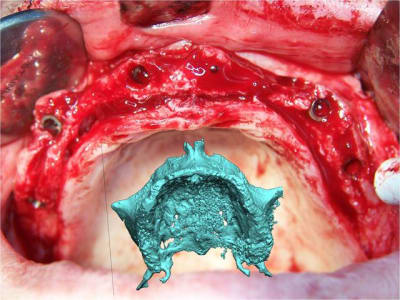

Expansion, condensation guidée

votre avis sur ce cas clinique

Le guide chirurgical, positionneur d’implants reste en place jusqu’à la pose des implants.

cicatrisation gingivale, suite expansion